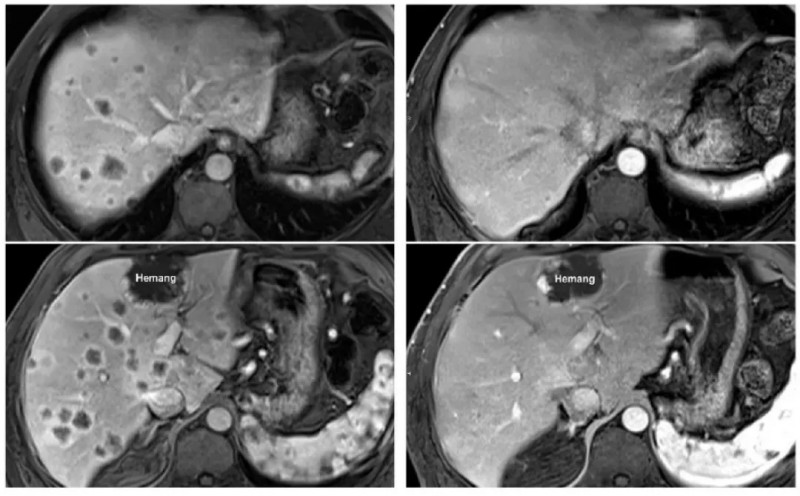

结果显示,总体患者根据严格的医学影像学标准(RECIST),确认的部分缓解率达到了15.1%。在联合了免疫检查点抑制剂(帕博利珠单抗)后,客观缓解率直接飙升至23.5%!

数据可能是冰冷的,但背后的真实案例却让人热血沸腾:

在随访中,有一位患有胰腺癌(被称为癌症之王,致死率极高)且已经转移至肝脏、淋巴结和腹膜的晚期患者。在接受了特定的TIL疗法联合治疗仅仅7个月后,他体内的1个肝转移病灶完全凭空消失,全身整体肿瘤面积大幅缩小了44.1%!

更令人拍案叫绝的是另一位胰腺癌晚期患者,在接受TIL回输后的仅仅6周内,影像学检查震惊了所有的主治医生——他肝脏上密密麻麻的数十个转移瘤,竟然不可思议地全部完全消退!